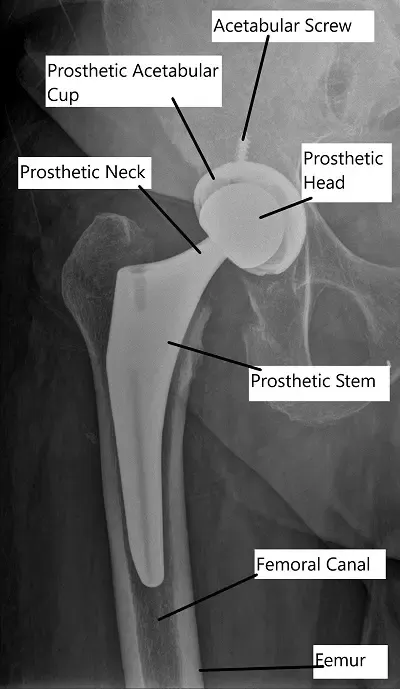

Anterior hip replacement surgery requires general anesthetic – once this has been administered, a surgical approach using the anterior skin directly overlying the hip is used. The surgeon then parts the muscles in this area without cutting them and exposes the hip capsule. This will then be opened and the arthritic femoral head will be removed. The acetabulum will be prepared for its replacement component by grinding away the arthritic bone with a special tool, and once it is placed in position, it may be held in place with one or more bone screws.

X-ray showing Total Hip Replacement in AP view

Once this is completed, some further surgical dissection is necessary to expose the proximal femur and this includes releasing some of the capsule and tendons from the posterior part of the cut end of the femur.

Once retractors are placed and visualization of the proximal femur is adequate, other special tools can be used to determine the correct size of replacement component for each patient. X-rays are used to help determine the appropriate position and size of the implant intraoperatively. It is also used to help the surgeon determine that the length of the leg is equal to the other side once the right size component has been selected.

Can you explain the role of X-rays during the procedure and in postoperative assessment?

X-rays are used intraoperatively to assess implant positioning and ensure accurate placement. Postoperatively, X-rays are utilized to evaluate implant stability, detect any abnormalities, and monitor healing progress.